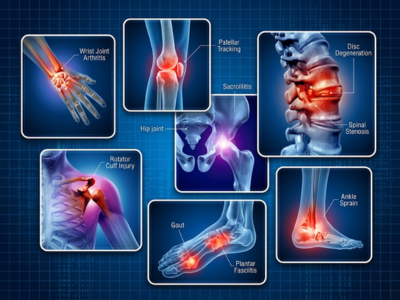

Orthopedic conditions affect the body’s musculoskeletal system, including bones, joints, muscles, ligaments, and tendons. Issues such as arthritis, back pain, fractures, and sports injuries can significantly impact mobility and quality of life if not addressed on time. Depending on the severity, treatment may include medications, physiotherapy, or advanced surgical procedures to restore function and mobility.

Not sure if your condition needs orthopedic care? Here’s what we treat at our orthopedic hospital in Navi Mumbai.

Orthopedic Conditions Treated at Echelon Hospital

Arthritis

Management of osteoarthritis and rheumatoid arthritis to reduce pain, improve joint function, and enhance mobility.

Fractures and Dislocations

Management of both complex and simple bone injuries to achieve proper alignment and fast recovery.

Spine Disorders

Care for conditions like herniated discs, sciatica, and spinal stenosis using advanced medical and surgical options.

Sports Injuries

Conservative as well as surgical treatments for various sports injuries including ligament tears such as PCL/ACL, tendon injuries and muscle strains.

Osteoporosis

Focused care to strengthen bones, prevent fractures, and manage bone density loss through medication and lifestyle changes.

Chronic Back or Neck Pain

Effective treatment to overcome back or neck pain due to posture issues, injury or age-related degeneration.

Joint pain and stiffness

Evaluation and treatment of painful joints that cause difficulties in moving.

Ligament or tendon injuries

Specialized treatment to restore function and stability after soft tissue injuries.

Post-traumatic Conditions

Care to prevent complications following an injury such as muscle stiffness, weakness and other abnormalities.

Degenerative joint diseases

Treatment for age-related joint wear and tear to improve comfort and quality of life.